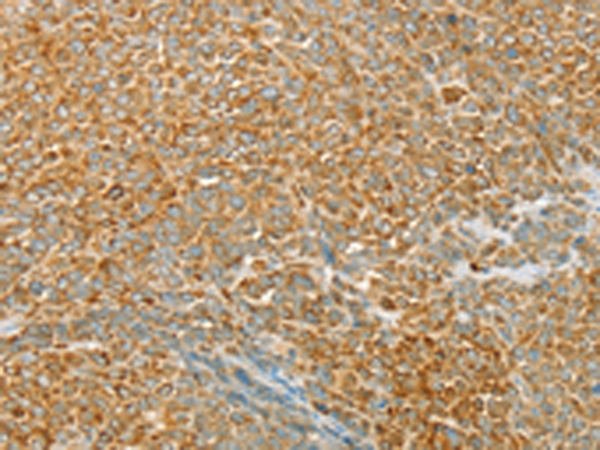

分类: 科研抗体货号: P01696别名:应用: WB,IHC反应种属: Human, Mouse